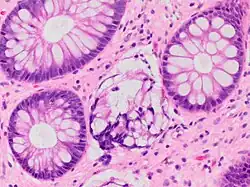

| A micrograph demonstrating cryptitis, a microscopic correlate of colitis. H&E stain. | |

An important investigation in the assessment of colitis is biopsy for histopathology. A very small piece of tissue (usually about 2mm) is removed from the bowel mucosa during endoscopy and examined under the microscope by a histopathologist. A biopsy report generally does not state the diagnosis, but should state any presence of chronic colitis, give an indication of disease activity, as well as state the presence of any epithelial damage (erosions and ulcerations).[6]

Histopathology findings generally associated with chronic colitis include:[6]

Crypt degeneration -

Crypt branching and other architectural distortions -

Paneth cell (pictured) or gastric metaplasia (only applies in the left colon and rectum)

Other findings include basal plasmacytosis and mucin depletion.[6] Histopathology findings generally associated with active colitis include:[6]

-

Neutrophilic cryptitis (neutrophils within crypt epithelium) -

Crypt abscesses (luminal neutrophilic aggregates) -

Gland destruction -

Ulceration (seen here as absence of epithelium, and granulation tissue with many fibroblasts)